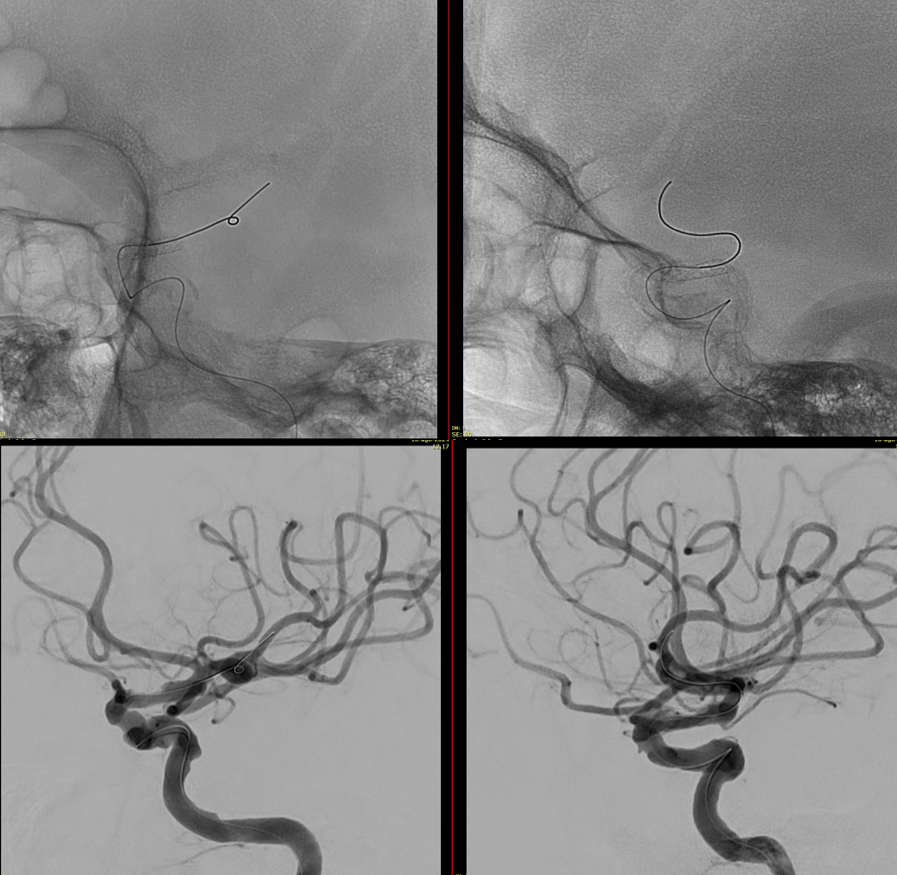

If you want to use a balloon-mounted self-expanding stent here, your call. In our book, this is a balloon-mounted case any day. Yes, yes, the brain is not the heart. But for this problem, there is a reason balloon-mounted stents now rule, and they tried self-expanding ones at the beginning also…